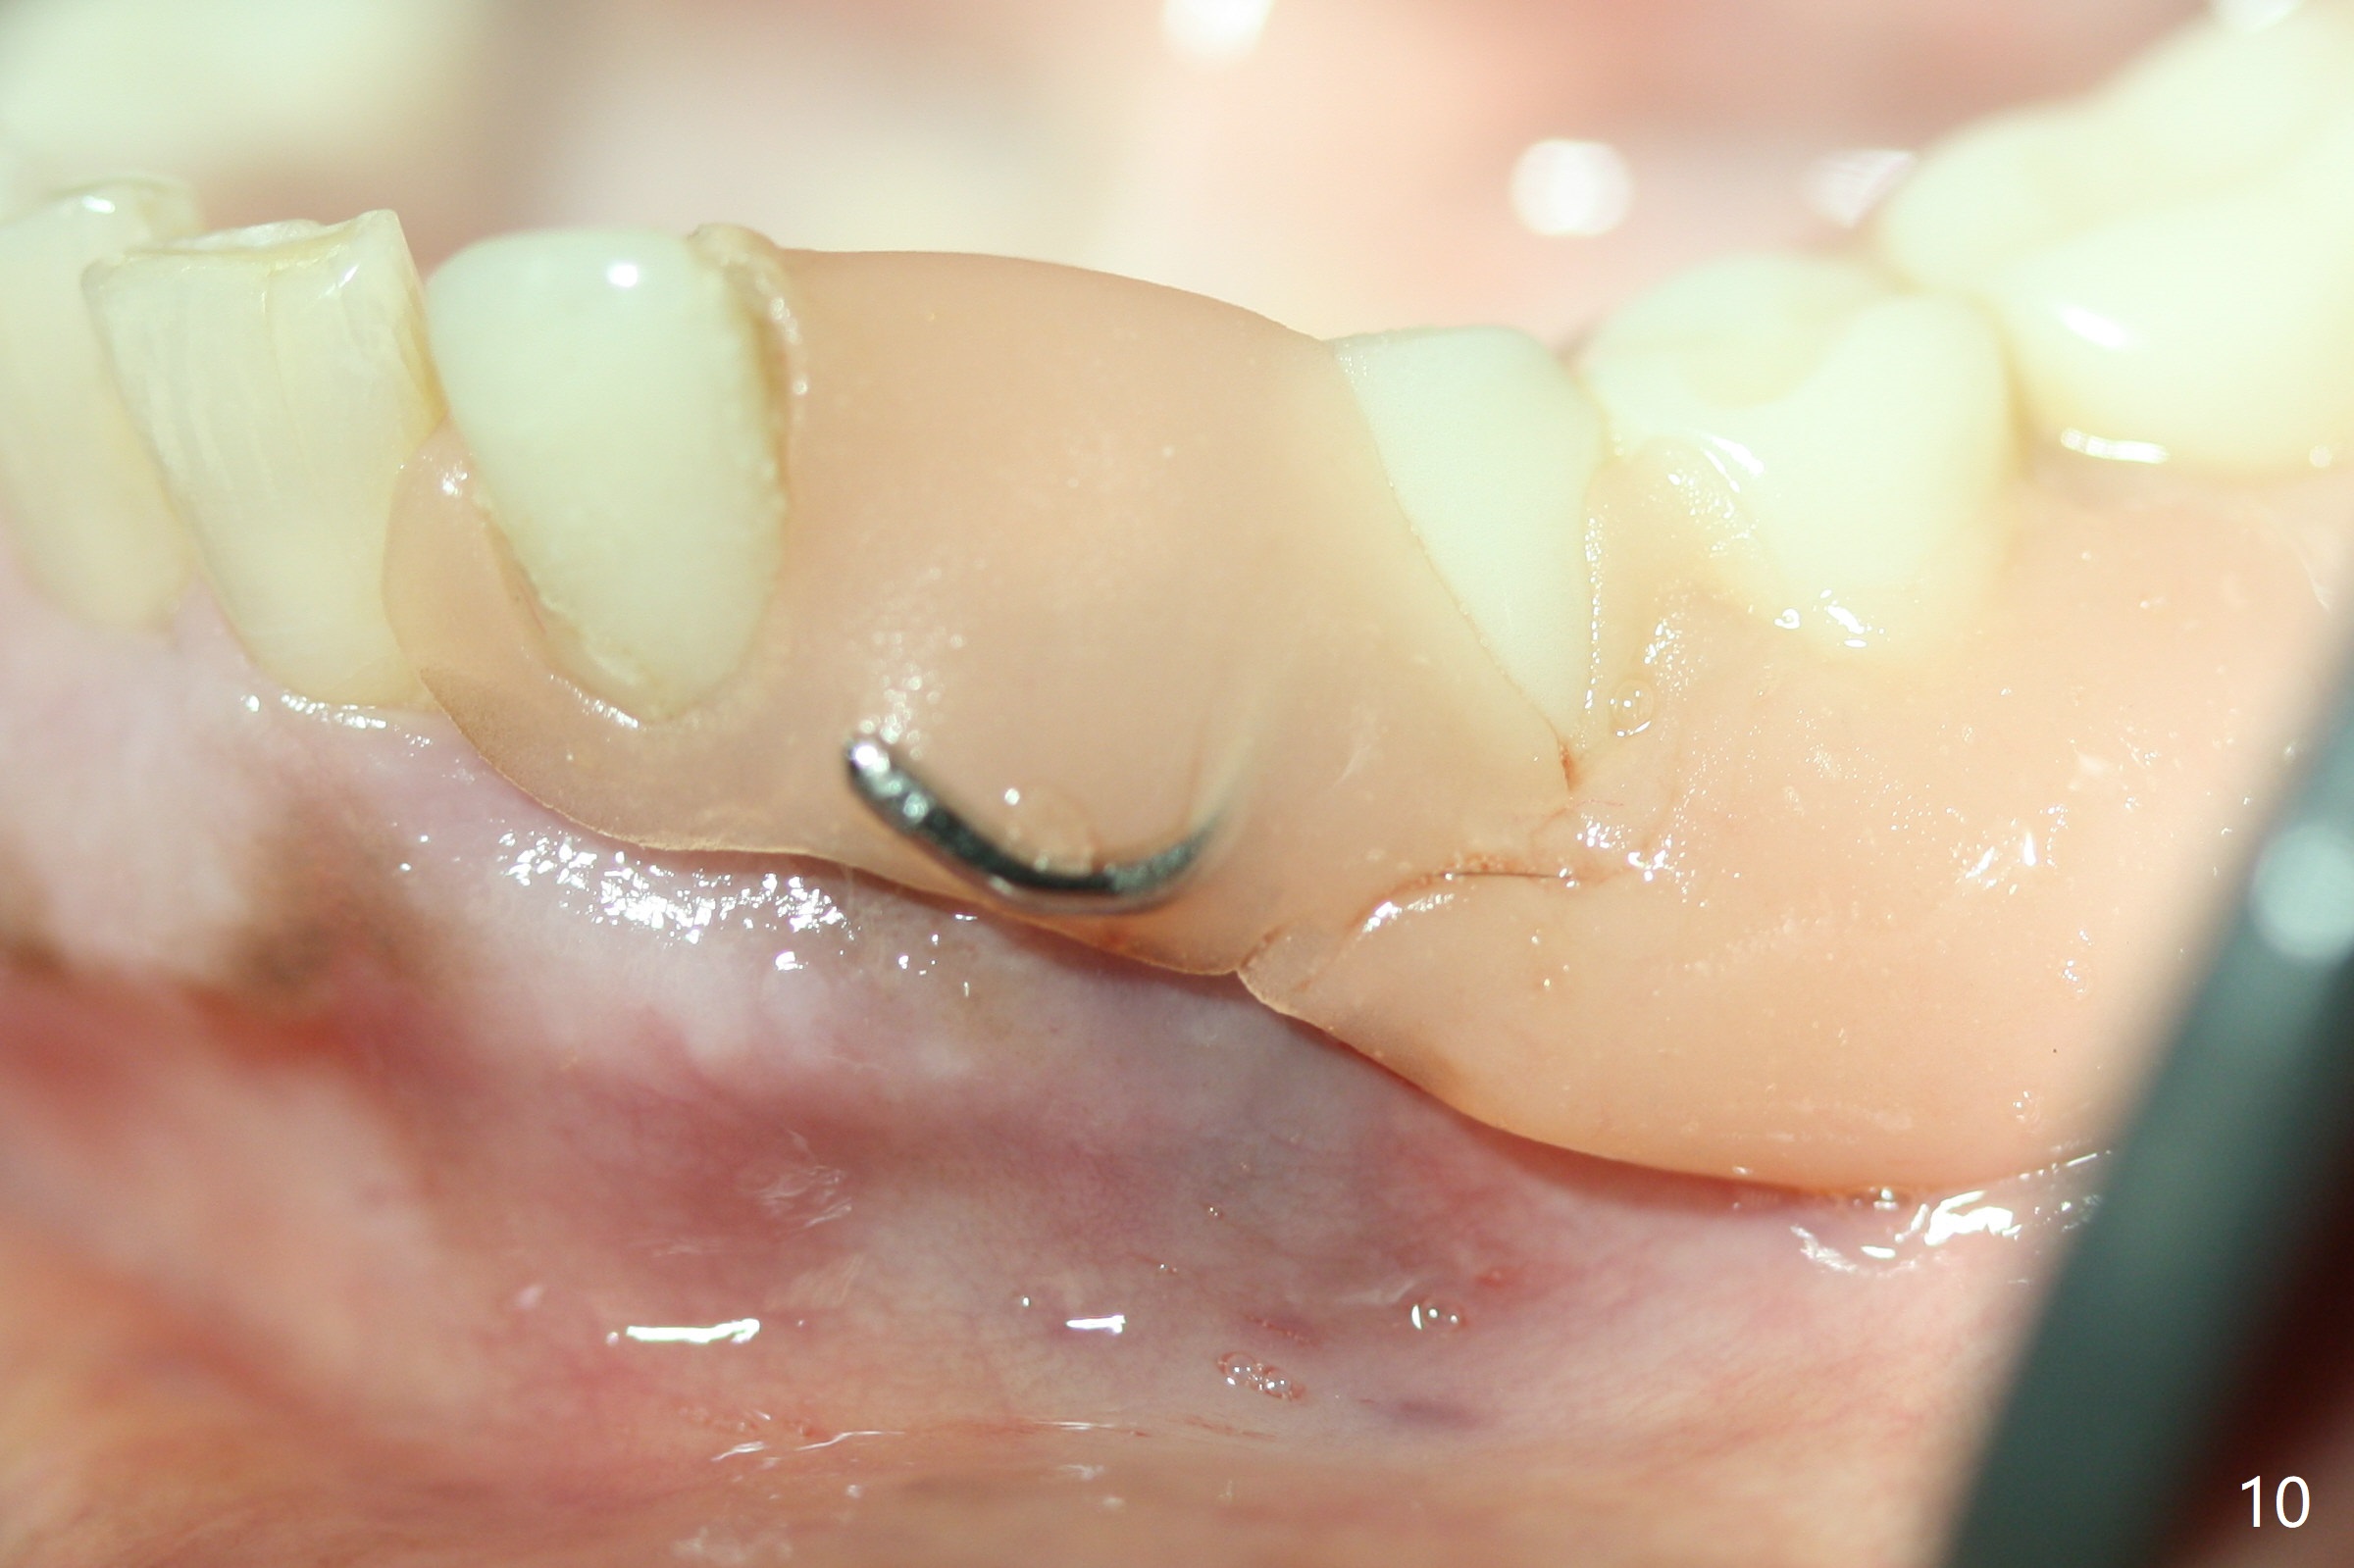

The inflammation around the tooth #22 (Fig.1 *) and mobility may be related to trauma from the only clasp of the lower flipper (Fig.2). The latter is loose with space underneath (>) and laterally (Fig.3 *). The distobuccal plate is defective upon extraction; the osteotomy is initiated in the mesiolingual slope of the socket (Fig.4) with ~ 6 mm native bone. When a 3.8x15 mm dummy implant achieves insertion torque of 50 Ncm, the insertion is incomplete with apical space (Fig.5 *). The definitive implant (3.8x13 mm) closes the apical space and obtains insertion torque >55 Ncm; a ball abutment with 2 mm cuff seems to be short for retention (Fig.6). A 4.5x4(5) mm cemented abutment (Fig.7,8) seems appropriate for retention after soft reline of the lower flipper (Fig.9-11). The socket heals without bone graft exposure 8 days postop (Fig.12,13). To satisfy the patient's desire to have a white tooth, the buccal portion of the soft reline and the abutment is removed (Fig.14) and a crown form is added (Fig.15 *). The socket obliterates 3 months postop (Fig.16).